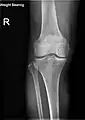

Radiography to examine possible fractures after a knee injury

Knee fractures are rare but do occur, especially as a result of a road accident. Knee fractures include a patella fracture, and a type of avulsion fracture called a Segond fracture. There is usually immediate pain and swelling, and a difficulty or inability to stand on the leg. The muscles go into spasm and even the slightest movements are painful. X-rays can easily confirm the injury and surgery will depend on the degree of displacement and type of fracture.